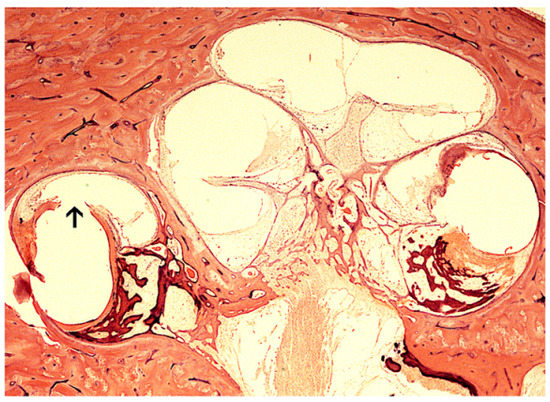

| Kamakura and Nadol [11] | 17 HTB histopathology | 17 / 17 had fibrous tissue and new bone formation. Positive correlation between SGN count and speech scores. % Volume of new tissue increased with damage to the basilar membrane. |

| Li et al. [22] | 12 HTB | Fibroosseous change in 12/ 12 and greater if there was lateral wall damage. |

| Linthicum et al. [12] | 22 HTB from 13 patients | All had varied amount of fibrosis, and some had ossification, mostly basal. One HTB 14 years post implantation. |

| Seyyedi and Nadol [13] | 28 HTB from 21 patients | 96,4% had varying degrees of new tissue formation. 25% had eosinophilic infiltrate. Foreign-body giant cell formation and lymphocytic infiltration at cochleostomy site and electrodes. |